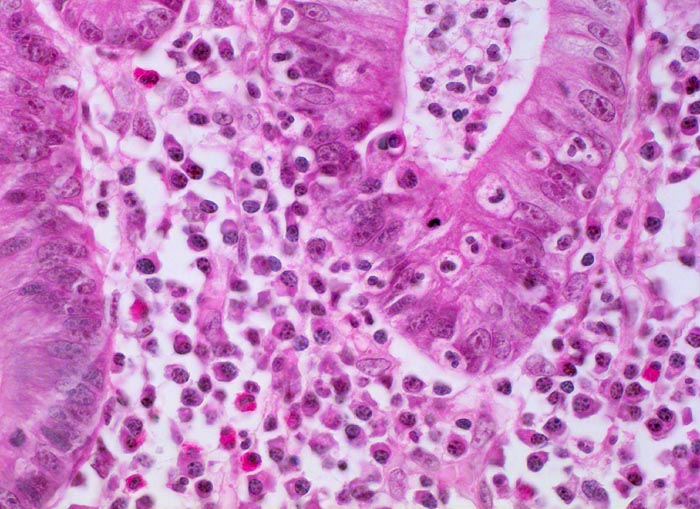

Colitis ulcerosa: Kryptitis

Neutrophile Granulozyten infiltrieren das Kryptenepithel (=Kryptitis). Verdichtetes Entzündungsinfiltrat in der Lamina propria bestehend aus zahlreichen Plasmazellen mit exzentrisch gelagerten Kernen, neutrophilen Granulozyten und eosinophilen Granulozyten. Die Krypte enthält zusätzlich einen Kryptenabszess. Das Kryptenepithel zeigt eine deutlich reduzierte Schleimbildung, das Zytoplasma der Epithelzellen ist basophil und die Kerne zeigen reaktive Atypien (Vergrösserung und Abrundung des Kerns, Hyperchromasie, grosse Nukleolen).

Kolektomie wegen chronischer therapierefraktärer Kolitis.

400